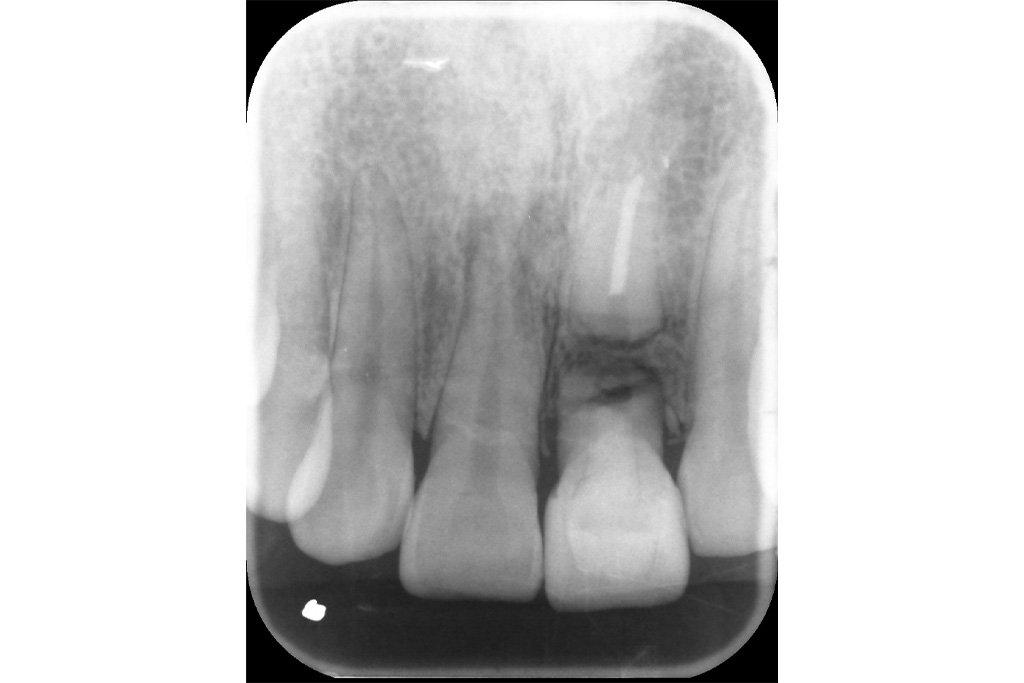

治療前